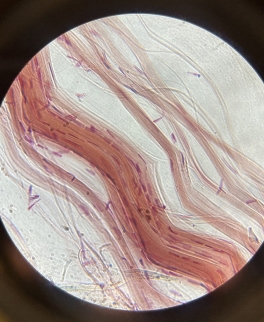

Dense Regular Elastic Connective Tissue (Elastic Tissue)